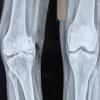

Three years later, the patient came to our orthopedic department due to anterior knee pain with difficulty in bending and extending the knee. She was clinically examined and the knee was found stable according to valgus, varus test. However, patellar instability was observed clinically and confirmed with X-rays (Merchant view) (Fig. 3). Initially, the patient was advised to undergo intensive physiotherapy, strengthening of the extensor mechanism and particularly the vastus medialis. Three months later, she presented with severe patellar pain and an inability to flex or extend the knee.

Postoperatively, we immobilized the knee with a thigh-calf brace at 30° of knee flexion for 4 weeks and the patient was advised to walk with partial weight-bearing using crutches. Then, a hinged knee brace was used, and the range of motion was gradually increased to 90° over the next 2 weeks. Finally, after 6 weeks, the brace was removed, and intensive physiotherapy was recommended with the goal of achieving full range of motion of the joint and full weight-bearing. One year postoperatively, the patient was revaluated at our department and was found to be pain free and with satisfactory range of motion of the knee joint up to approximately 100° of flexion. There were no clinical signs of patellar instability or subluxation and the patella was found centered in the trochlear groove on a Merchant X-ray view (Fig. 7).